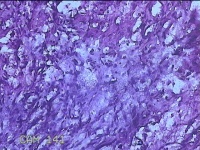

左大腿内侧包块

性别

男

年龄

21岁

临床诊断

脂肪瘤

一般病史

左大腿内侧起包块一月余。

标本名称

大体所见

灰白暗红色包块2.5x2x0.8cm一个,表面糜烂,切开包块呈实性,切面灰白暗红色,质软。

图1

图2